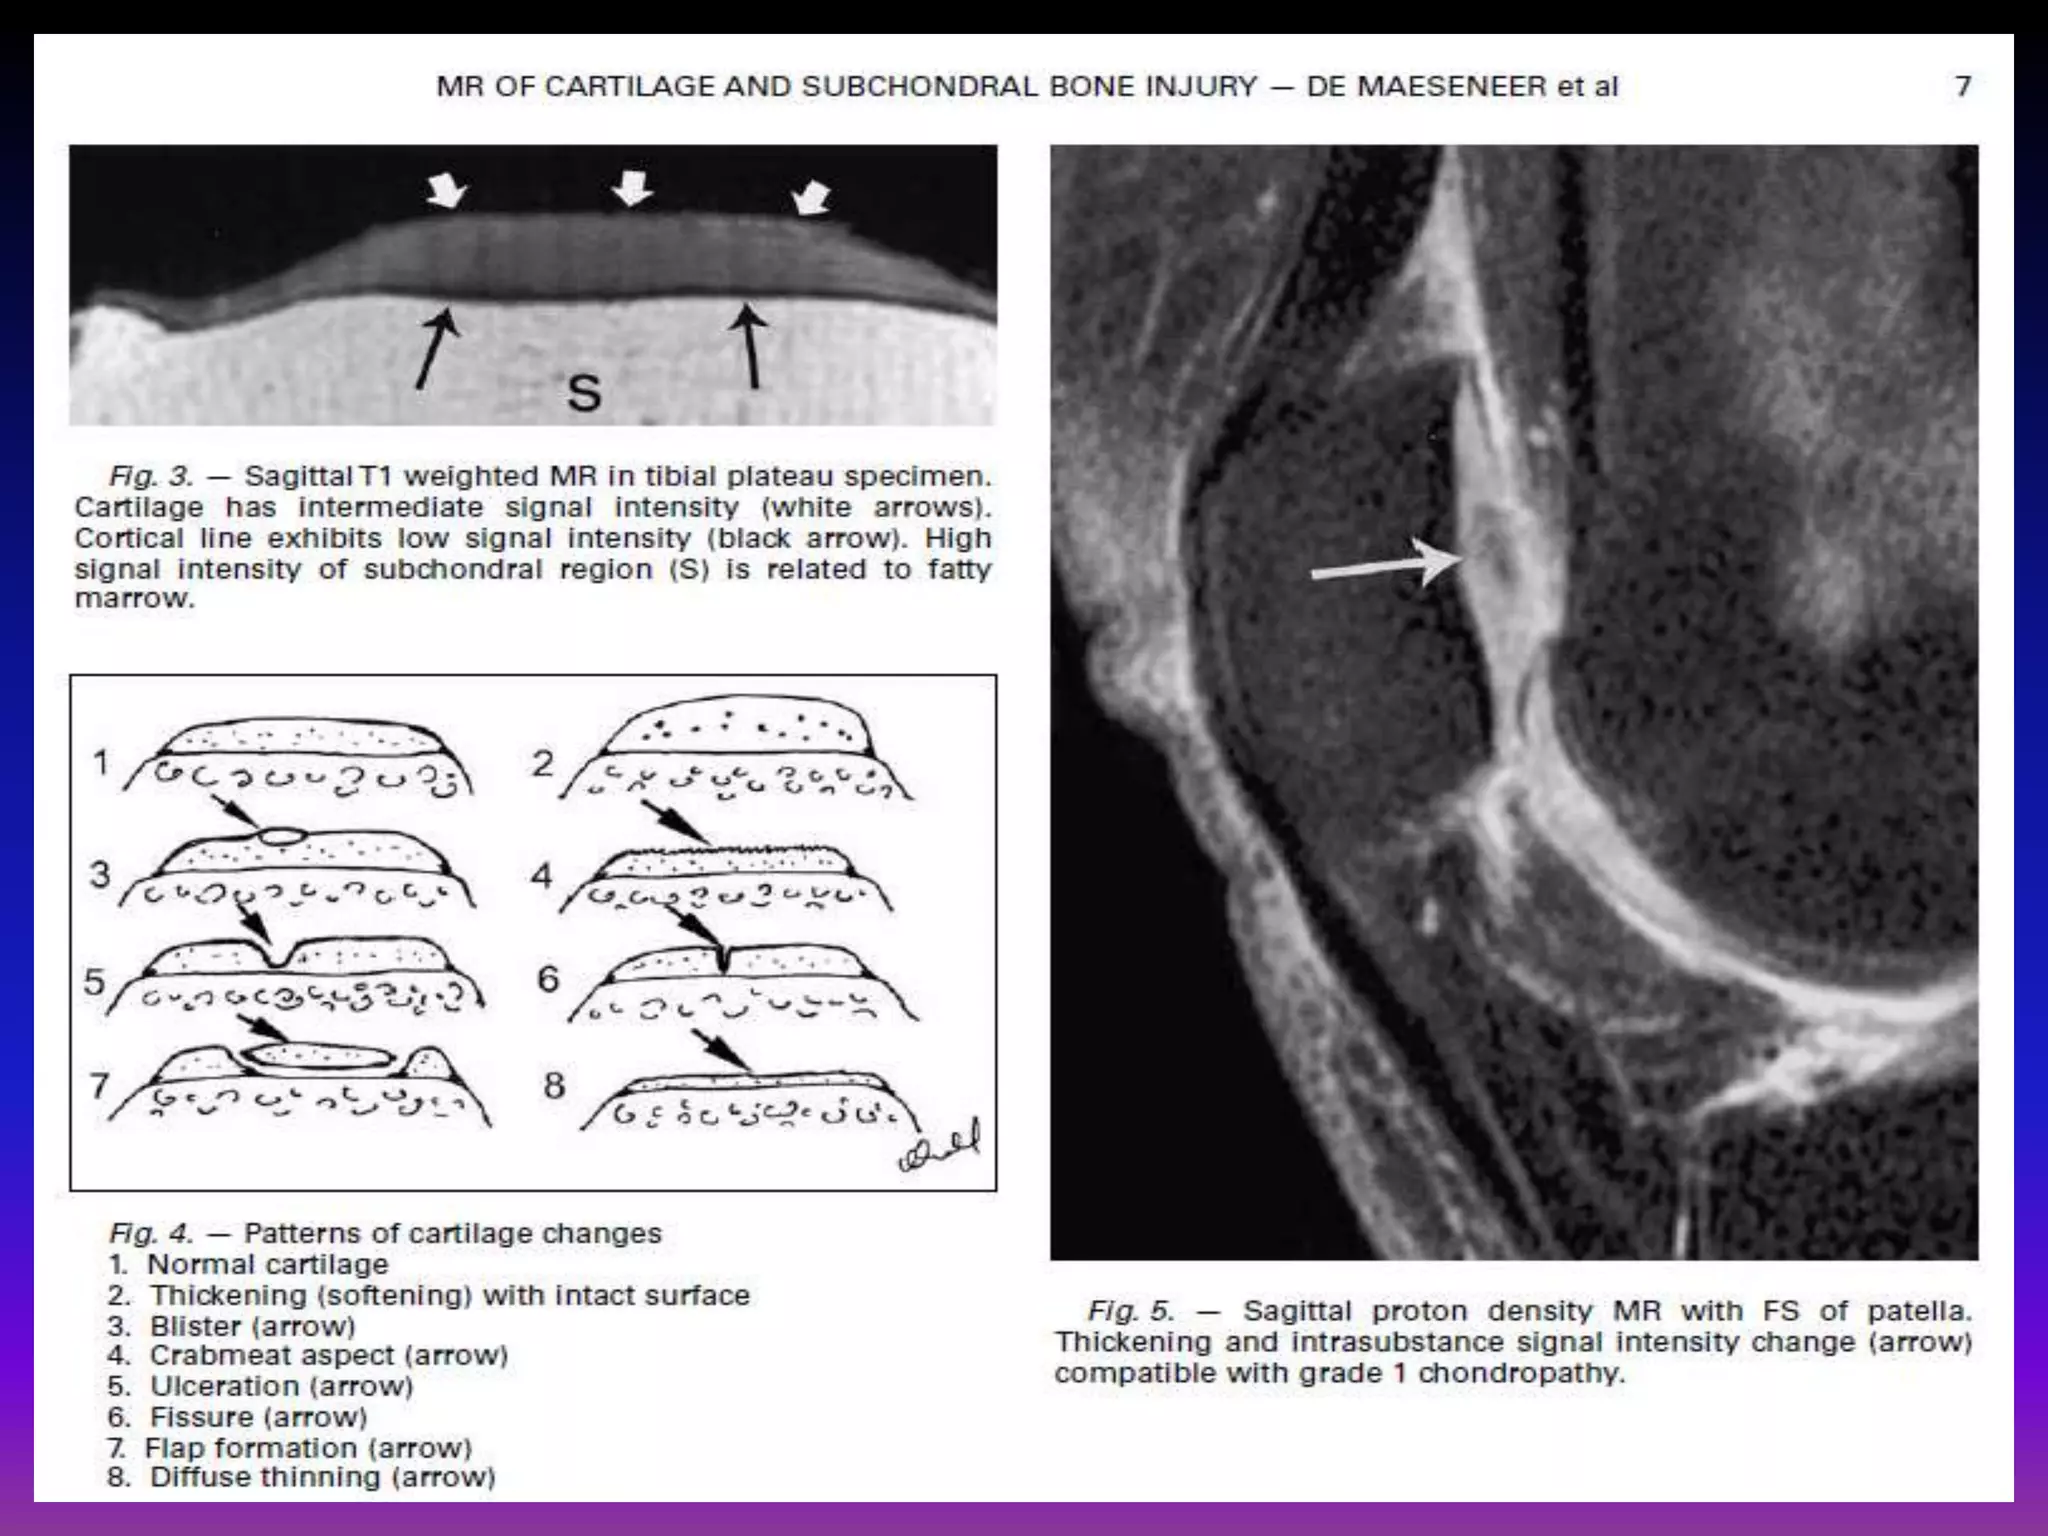

Chondromalacia can be divided into 4 grades by MRI, typically using fat

saturated proton density sequences. This grading system is the modified

outer bridge grading system, which was devised for arthroscopy initially for

assessment of chondromalacia patella, but then modified and extended for

all chondral surfaces.

grade I.

Focal areas of hyperintensity with normal contour

arthroscopically : softening or swelling of cartilage.

grade II.

Blister-like swelling/ fraying of articular cartilage extending to surface

arthroscopically : fragmentation and fissuring within soft areas of

articular cartilage.

grade III.

Partial thickness cartilage loss with focal ulceration

arthroscopically : partial thickness cartilage loss with fibrillation (crab-

meat appearance).

grade IV.

Full thickness cartilage loss with underlying bone reactive changes

arthroscopically : cartilage destruction with exposed subchondral bone.

Mild diffuse increased intra-substance signal

within morphologically normal cartilage.

Patterns of subchondral changes

1. Focally thickened cortical line (arrow).

2. Focal semilunar subchondral change (arrow).

3. Focal impaction (arrow).

4. “Bowing” fracture (arrow).

5. Cyst (arrow).

6. Edema (arrow).

7. Diffuse linear branching changes (arrow).

8. Osteophyte (arrow).